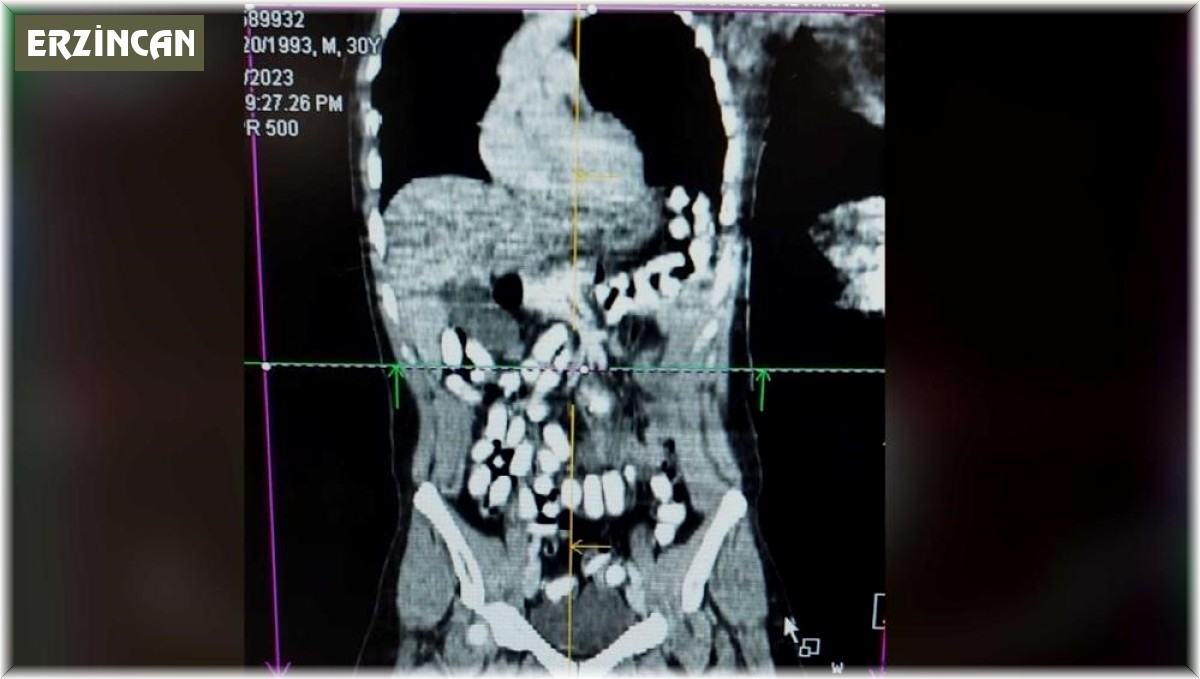

Erzincan - Erzincan İl Emniyet Müdürlüğü Narkotik Suçlarla Mücadele Şube Müdürlüğü ekiplerince, uyuşturucu ve uyarıcı maddelerin imal ve ticareti veya temini, gerek kullanmak için satın alınması, kabul edilmesi veya bulundurulması, gerekse de kullanımının kolaylaştırılması veya özendirilmesi eylemlerine ilişkin yapılan çalışmalarda; Türk Ceza Kanunu 188'inci maddesi "Uyuşturucu veya uyarıcı madde imal ve ticareti" suçuna ilişkin polis uygulama noktasında durdurulan, bir araçta bulunan A. H. isimli İran uyruklu şüpheli alınan iç beden muayenesi kararına istinaden hekim gözetiminde çekilen tomografi neticesinde mide ve bağırsak kısmında 126 adet kapsül halinde daralı ağırlığı ise 977,60 gr Afyon sakızı ve 25 adet Metadon hap ele geçirildi.